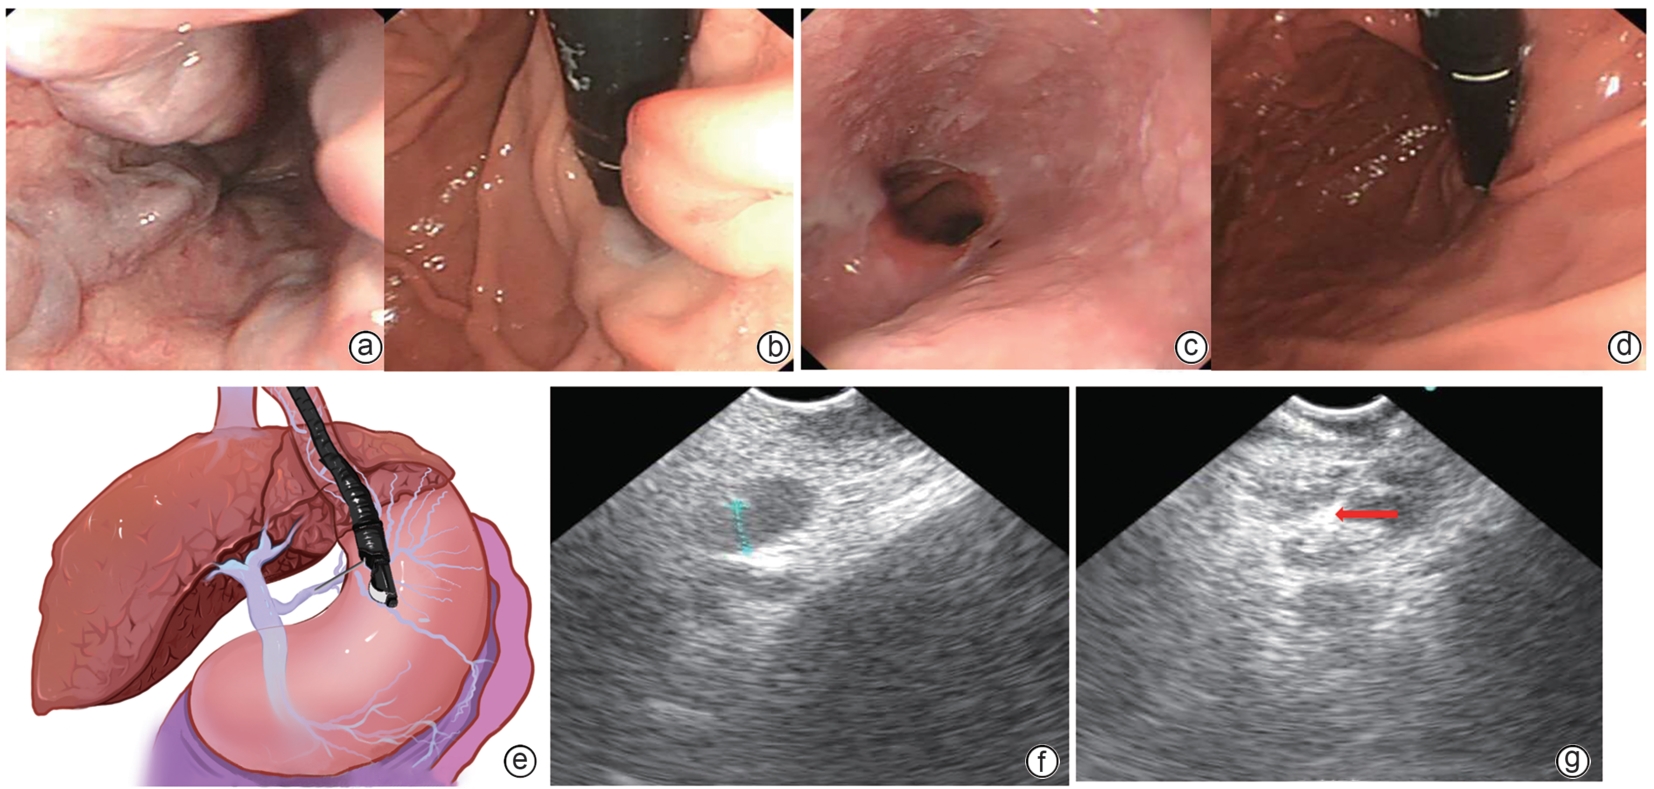

多学科管理模式对门静脉高压患者预后的影响

赖长祥, 唐奇远, 李知玉, 蒋育进, 周旋, 冼文杰, 陈瑞坤, 吴晓娟, 何清, 王方

2025, 41(10): 2068-2074. DOI: 10.12449/JCH251017

摘要:

目的  评估多学科团队(MDT)管理模式在改善肝硬化门静脉高压患者预后中的效果。  方法  纳入深圳市第三人民医院2022年5月—2024年7月入院的肝硬化门静脉高压患者86例,按照是否执行MDT治疗方案分为执行组(n=51)和未执行组(n=35)。收集患者基线临床资料,从入院到随访结束(随访截止时间为2025年1月),观察消化道出血、肝性脑病、肝癌、死亡结局发生情况。正态分布的计量资料两组间比较采用成组t检验;非正态分布的计量资料两组间比较采用Wilcoxon秩和检验。计数资料两组间比较采用χ2检验或Fisher精确检验。通过Kaplan-Meier法绘制生存曲线描述终点事件(消化道出血、肝性脑病、肝癌以及死亡)的累积发生率,采用Log-rank检验比较组间差异。Cox比例风险回归模型分析MDT管理对患者预后的影响。  结果  执行组与未执行组基线门静脉内径(t=1.216,P=0.017)、腹水(χ2=4.515,P=0.034)差异有统计学意义。所有患者平均随访(14.6±6.2)个月,生存曲线分析结果显示,两组消化道出血累积发生率差异有统计学意义(χ2=4.573,P=0.024),其余终点事件发生率差异均无统计学意义(P值均>0.05)。Cox回归分析显示,执行组消化道出血风险降低(HR=0.262,95%CI:0.110~0.630,P=0.003)。  结论  执行MDT治疗方案可显著降低肝硬化门静脉高压患者短期消化道出血风险,其长期效益需进一步随访验证。